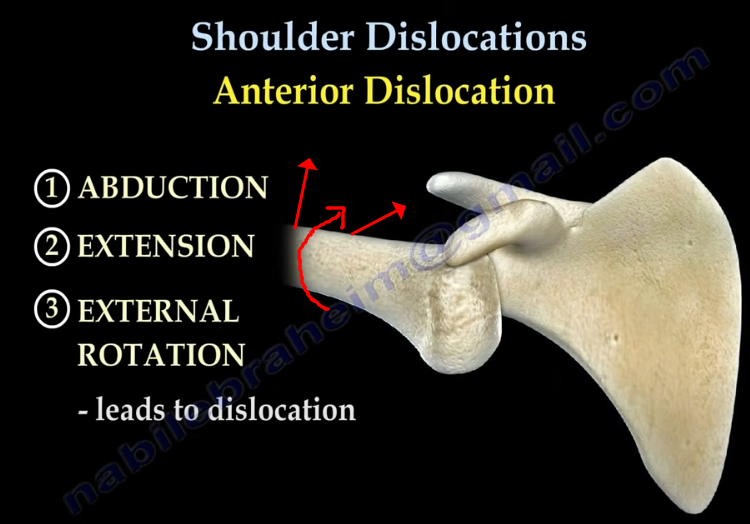

과도한 어깨 앞으로 빠짐상태인 전인 상태가 유지되고, 후인은 잘 되지않게되면 견관절의 관절와(Glenoid)에 해부학적문제가 아닌 기능적인 앞쪽기울어짐(fuctional anteversion)이 발생되면서 관절와순(Glenoid labrum)에 상완골두가 잘 밀착되지 않고 붕 뜨게 되면서 앞쪽 어깨의 안정성이 떨어지면서 손상에 취약하게 됩니다. 이는 결국 어깨 전방 탈구(Anterior dislocation, 어깨 탈구의 95% 차지, https://www.youtube.com/watch?v=xDePRKeB4kc)가 더 쉽게 발생할 수 있게됩니다.

참고로 어깨 앞쪽 전방탈구는 외전, 신전, 외회전 시 발생되며 위와같이 관절와의 기능적인 앞쪽 기울어짐상태 시 더 잘 발생할 수 있습니다.